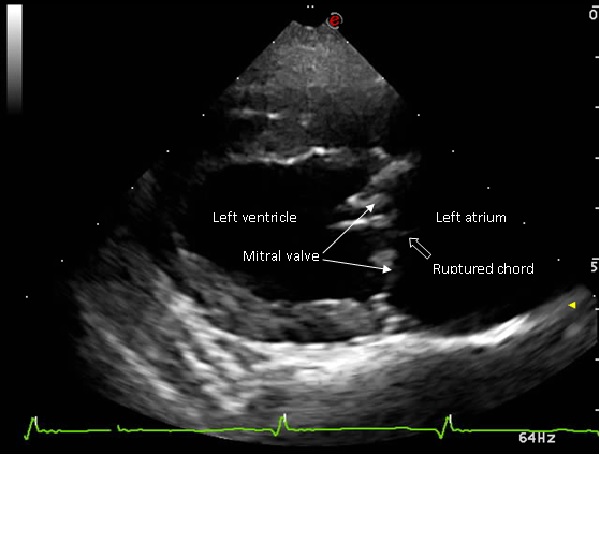

Heart mitral valve thickening and prolapse 01 ultrasound in Dogs Heart Valve Thickening It’s important to ask yourself about symptoms. Heart valve disease is when one or more of your heart valves do not work like they should. When doing so, don't simply think in terms of “yes” or “no,” but consider the degree to. The flaps of a valve may thicken, stiffen or fuse together. As a result, the valve cannot fully. Heart Valve Thickening.